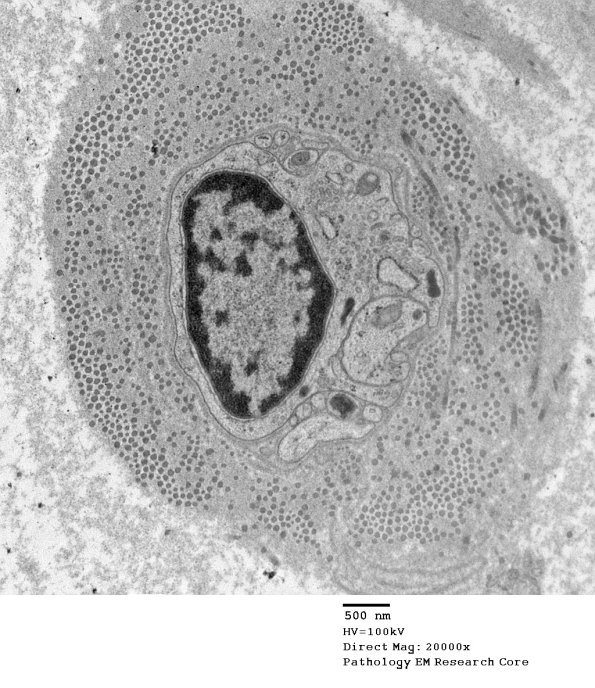

The central Schwann nucleus and processes are surrounded by collagen and oxytalan. (electron micrograph)